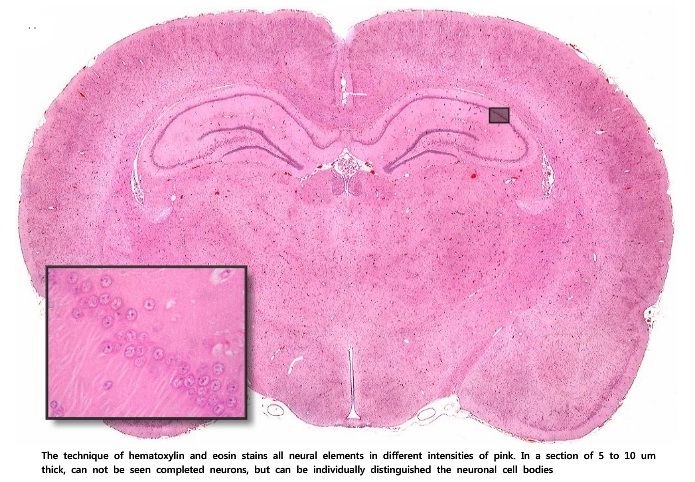

1. Hematoxilina eosina

1. Esta técnica tiñe todos los elementos nerviosos en diferentes intensidades de rosa y los núcleos celulares de color violeta. Como el corte es de grosor inferior al tamaño de la neurona (al igual que en otras técnicas que usan cortes de similar grosor), no se pueden ver neuronas completas, aunque si se pueden diferenciar los somas neuronales.

1. Corte : de 7 um de grosor